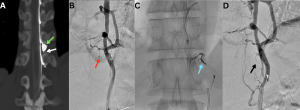

Fig 9: Clinical History: A 33-year-old woman with a several-week history of orthostatic headache, initially postural, with recent worsening associated with nausea and blurred vision.

Figure A. Axial post-contrast T1-weighted image demonstrating bilateral fronto-parietal subdural collections (red arrows), smooth pachymeningeal enhancement (green arrows) with thrombosis of the superior sagittal sinus (white arrow).

Figure B. MR venogram MIP image showing extensive venous sinus thrombosis involving the superior sagittal, inferior sagittal, straight, transverse, and sigmoid sinuses.

Figure C: Axial SWI reveals numerous prominent venous channels within the brain parenchyma, consistent with sequelae of chronic dural venous sinus thrombosis (blue arrow).